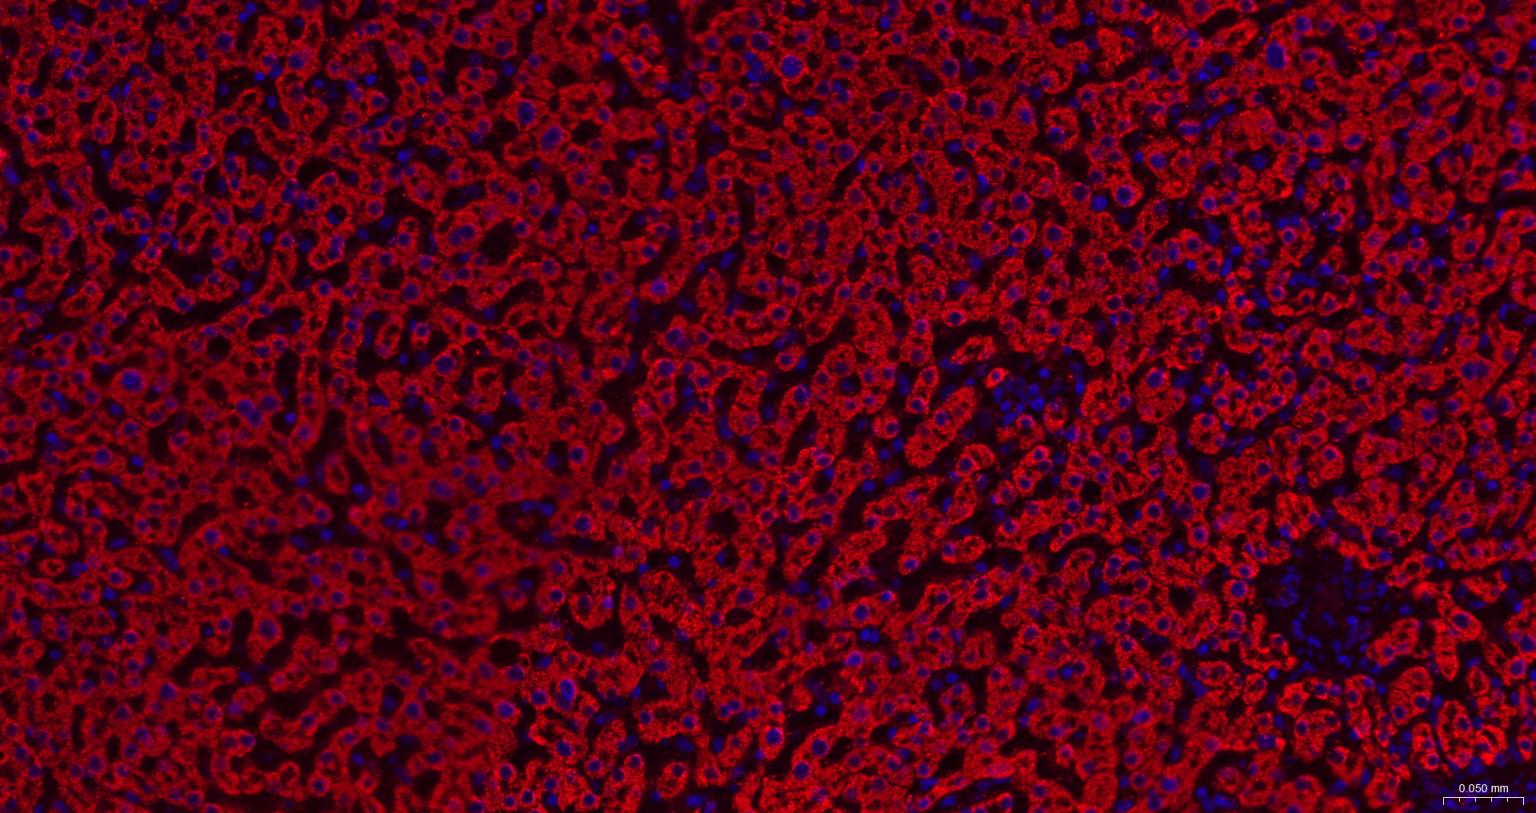

Paraformaldehyde-fixed, paraffin embedded Mouse Kidney; Antigen retrieval by boiling in sodium citrate buffer (pH6.0) for 15 min; The section was incubated with HSD17B10 Monoclonal Antibody, Unconjugated (bsm-61523R) at 1:200 overnight at 4°C. Followed by conjugated Goat Anti-Rabbit IgG antibody (Red, bs-0295G-BF594), DAPI (blue, C02-04002) was used to stain the cell nuclei.